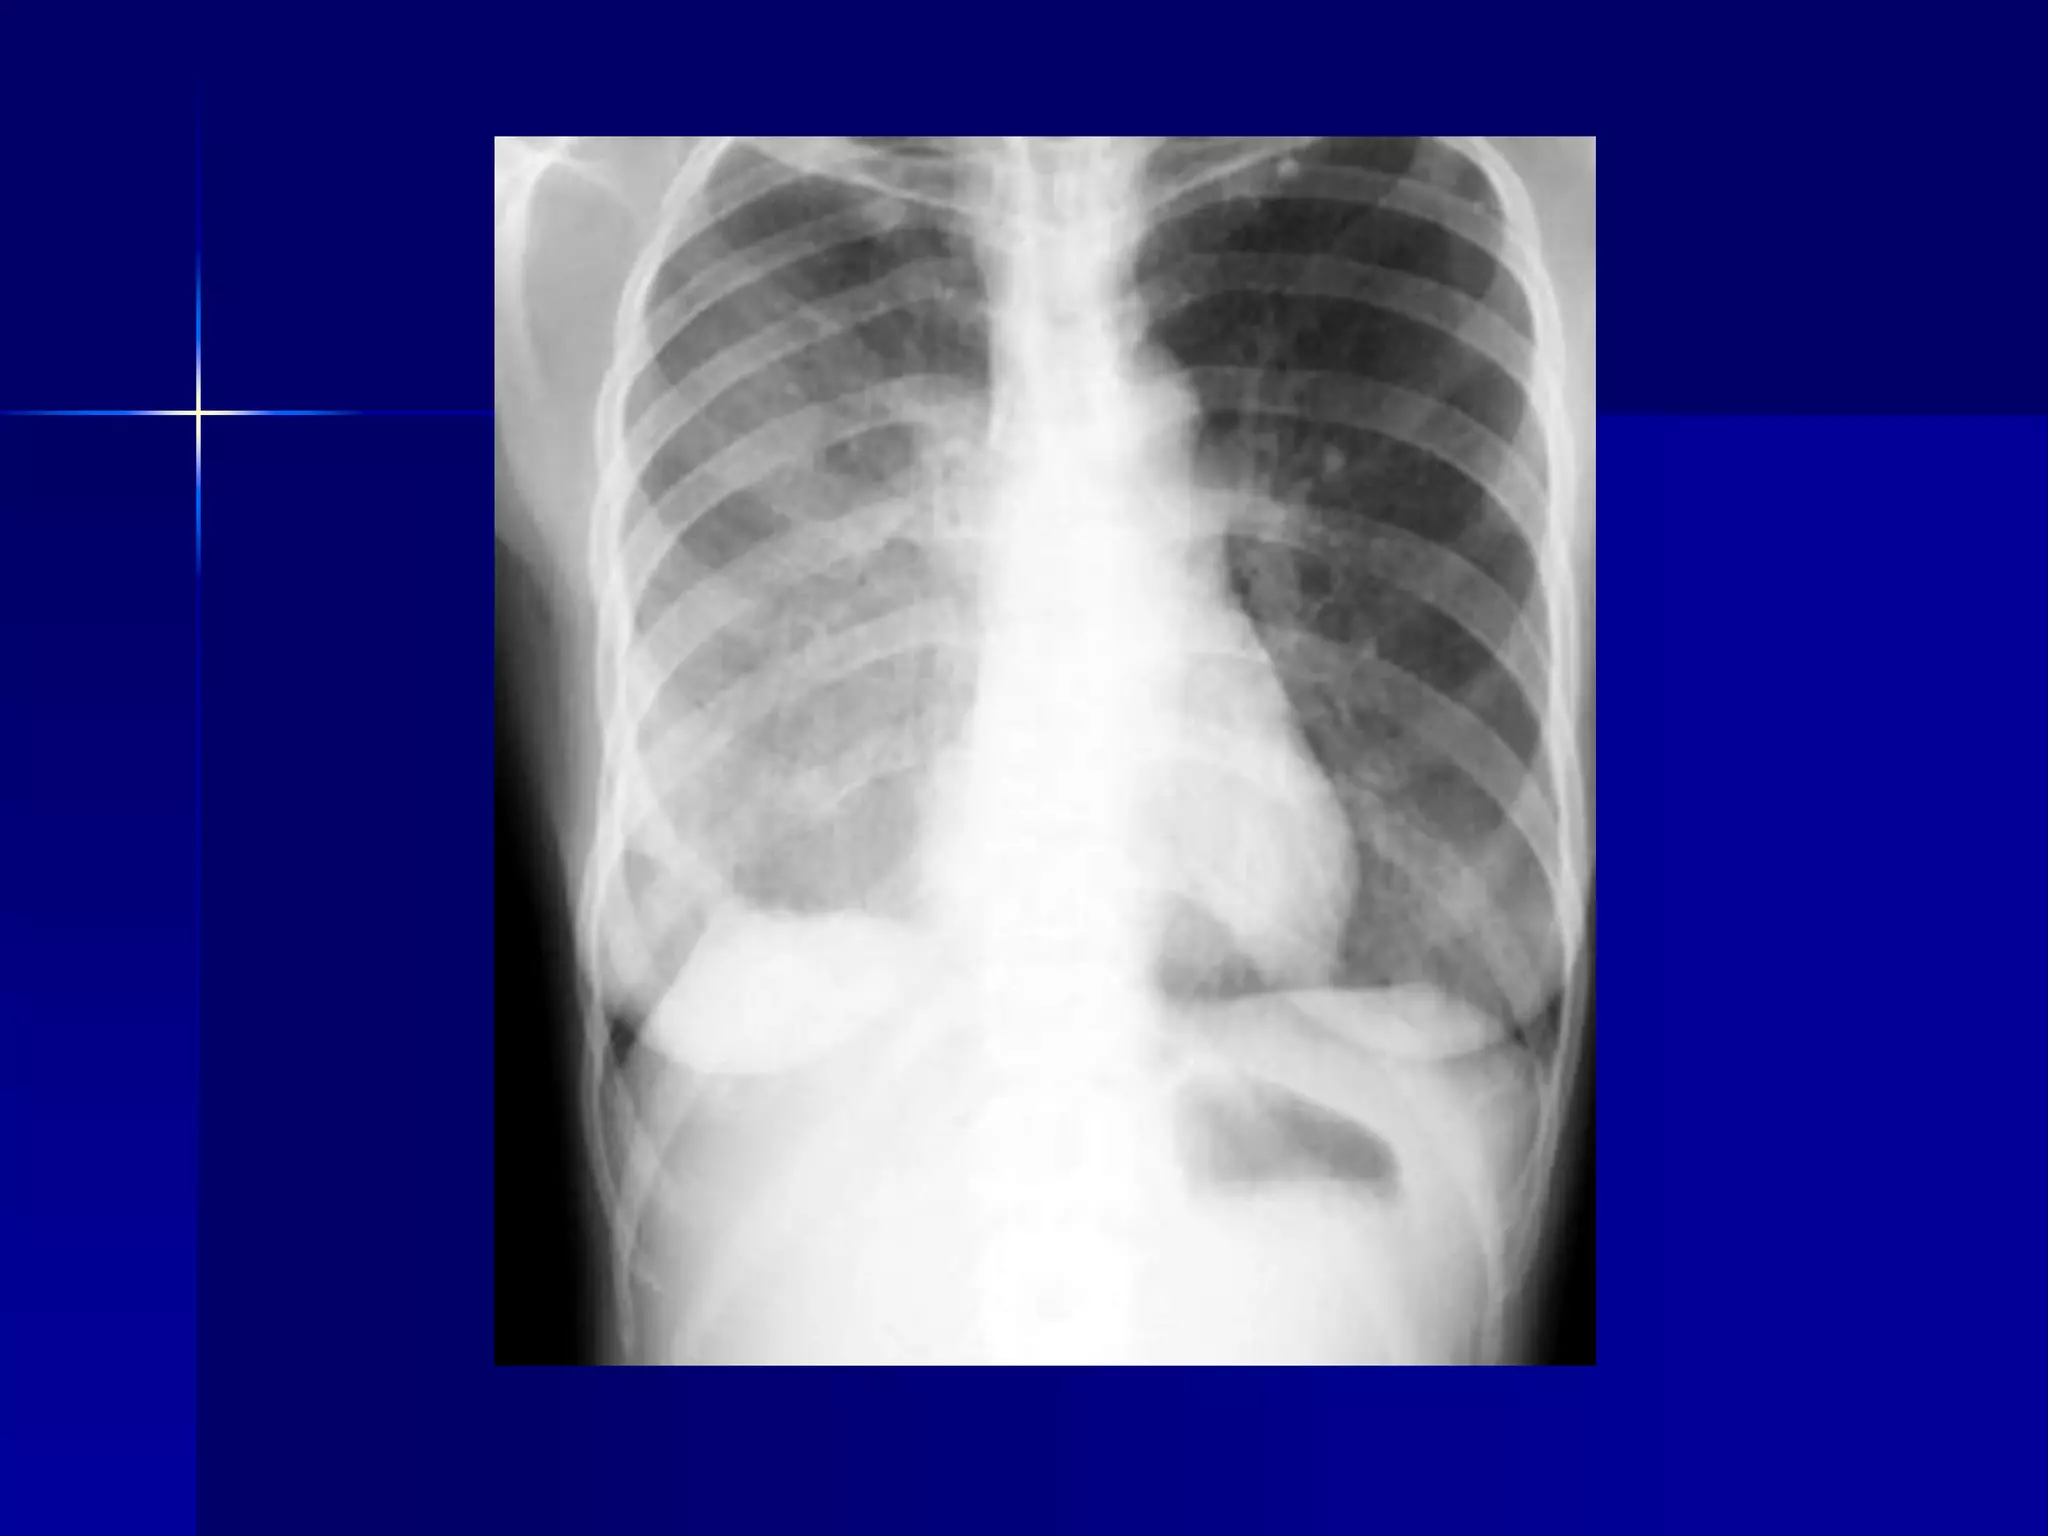

Atelectasis Right Lung

 Homogenous density right hemithorax

 Mediastinal shift to right

 Right heart and diaphragmatic

silhouette are not identifiable